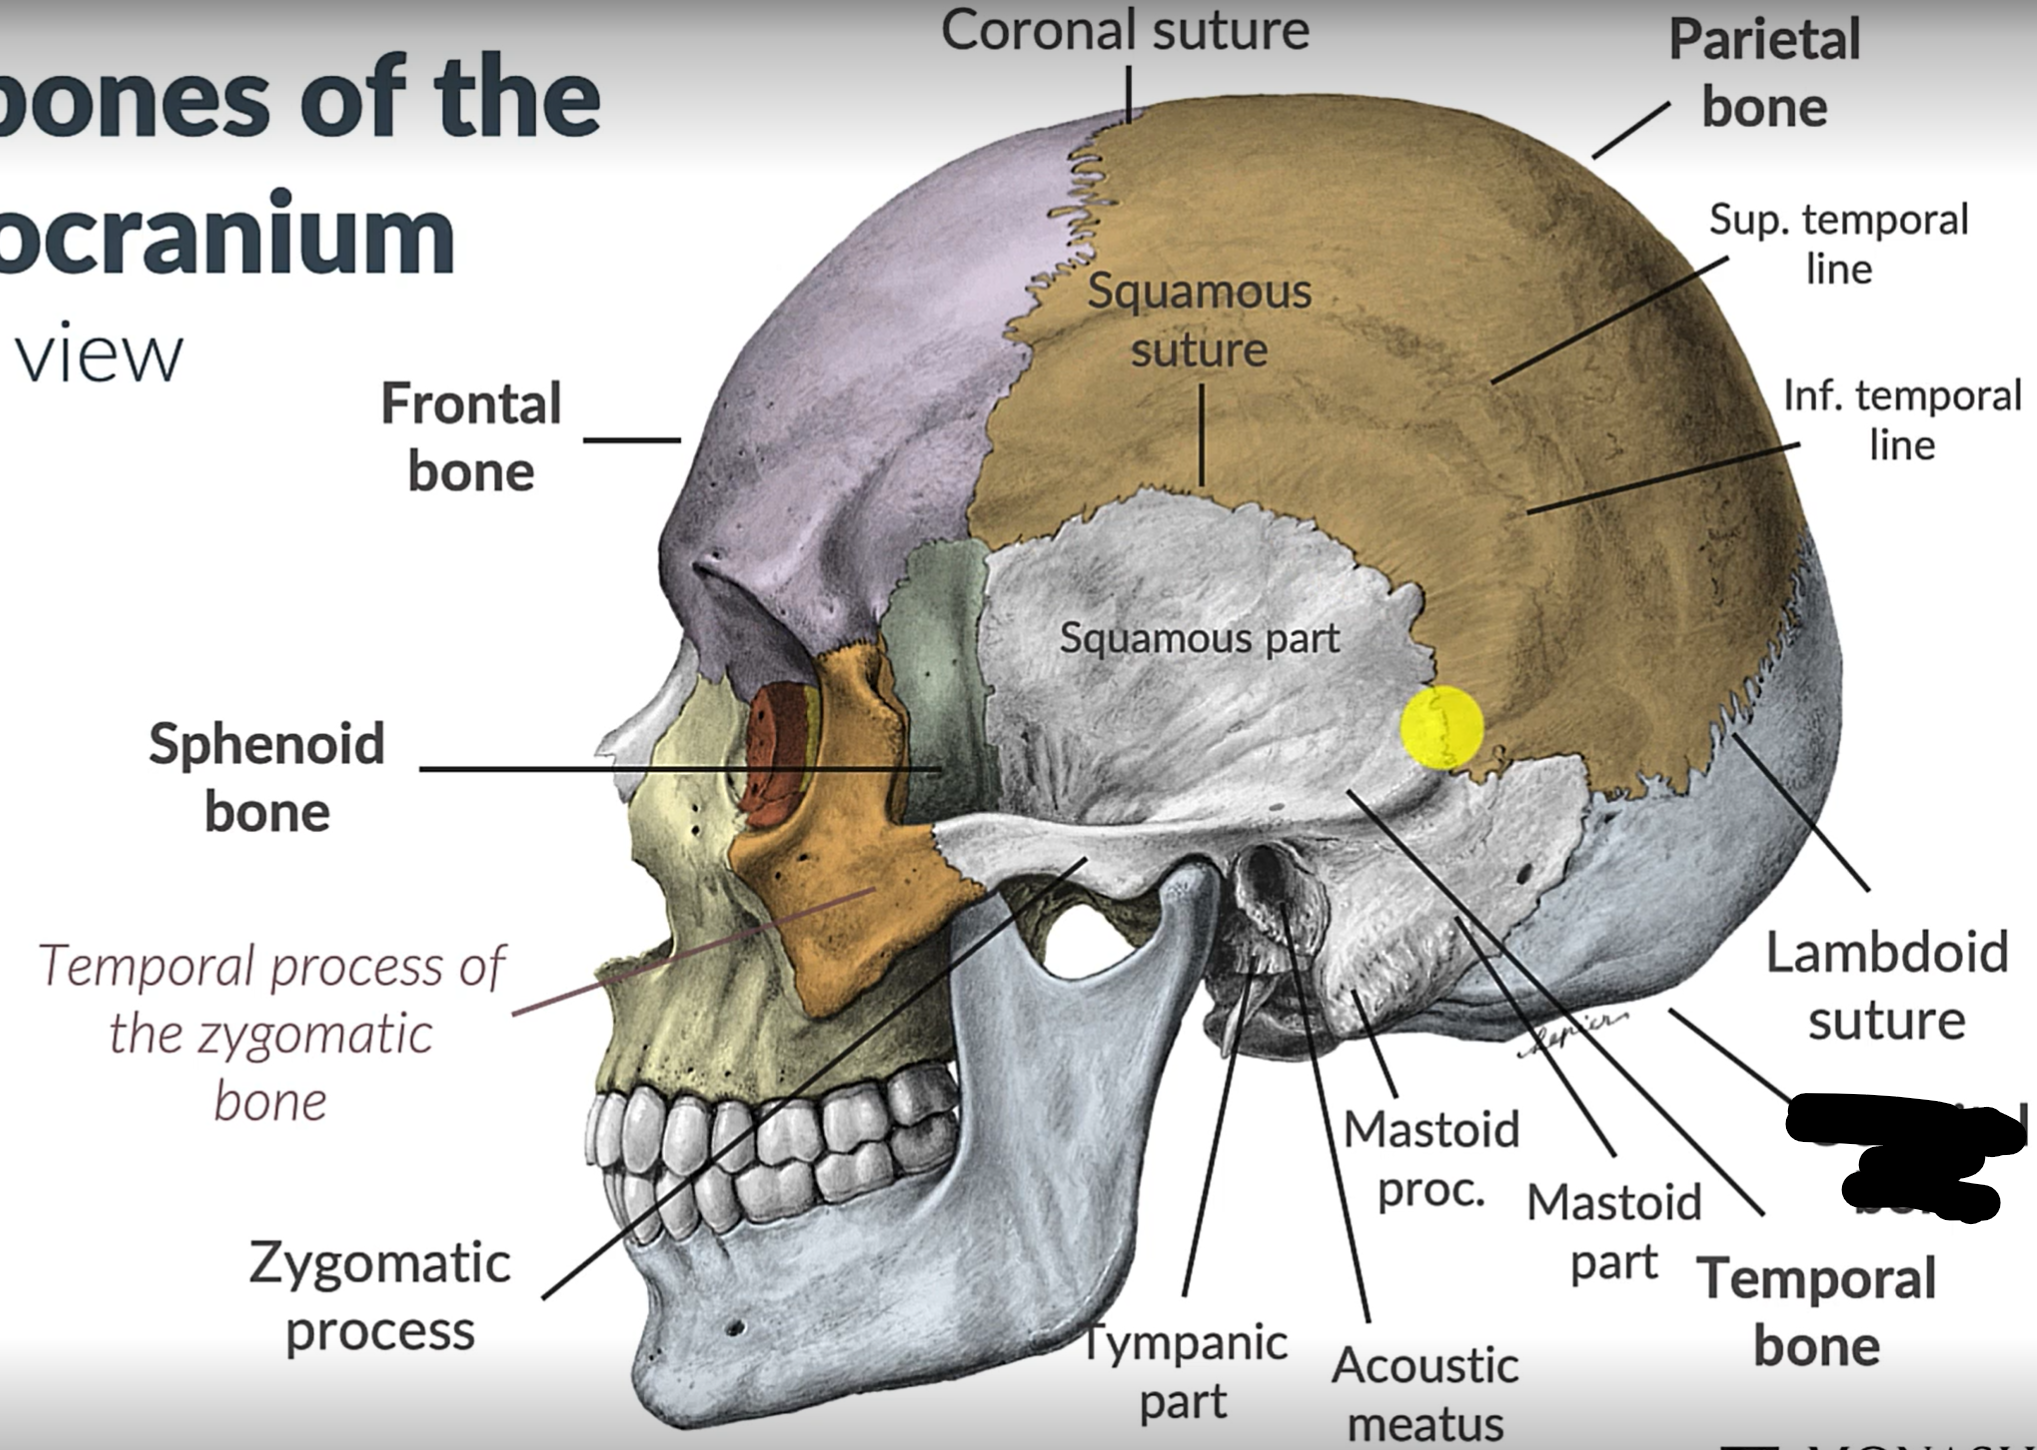

What bones make up the neurocranium?

Occipital bone (1)

Parietal bones (2)

Frontal bone (1)

Temporal bones (2)

Sphenoid (1)

Ethmoid (1)

What are the 4 cranial sutures and what do they separate?

Lambdoid - separates occipital from parietal and temporal

Sagittal - extends between parietal bones

Coronal - divides frontal and parietal bones

Squamous - either side of cranium, separates temporal and parietal bones

What is the pterion?

The point where the frontal, parietal, sphenoid and temporal bones meet.

Pterion